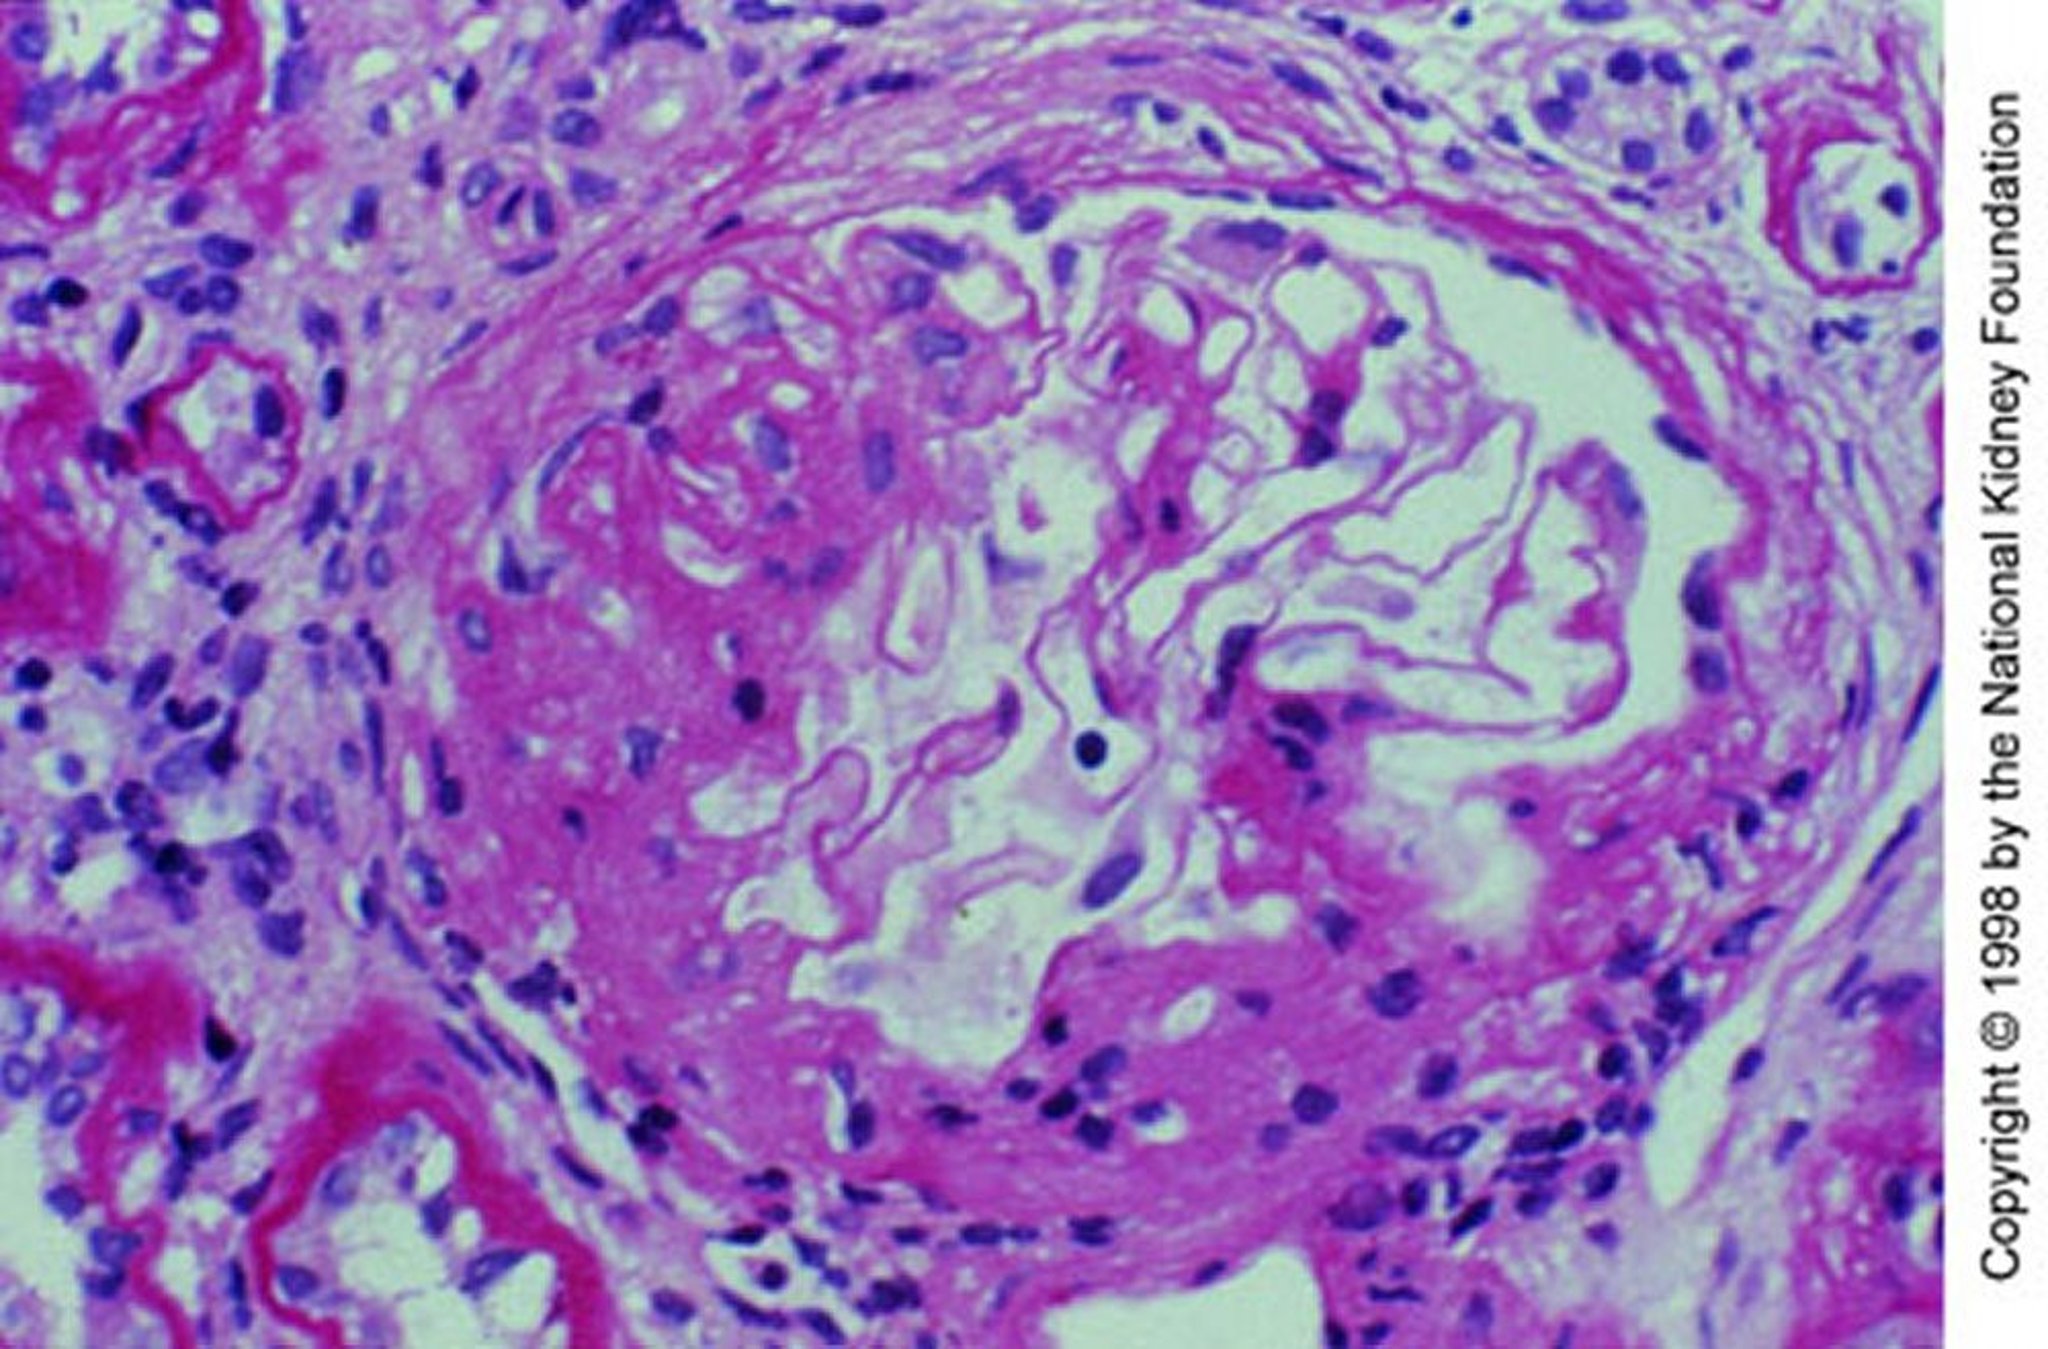

IgA-нефропатия (мезангиальная экспансия)

Мезангиальная экспансия при сегментарном склерозе (реактив Шиффа, ×200).

Image provided by Agnes Fogo, MD, and the American Journal of Kidney Diseases' Atlas of Renal Pathology (see www.ajkd.org).